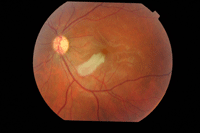

En la exploración fundoscópica se aprecia un blanqueamiento retiniano de origen isquémico inmediatamente después de la oclusión. Suele observarse en la mácula una mancha “rojo cereza” (

Figura 3).

Figura 3. OACR con importante palidez retiniana y mancha rojo cereza.